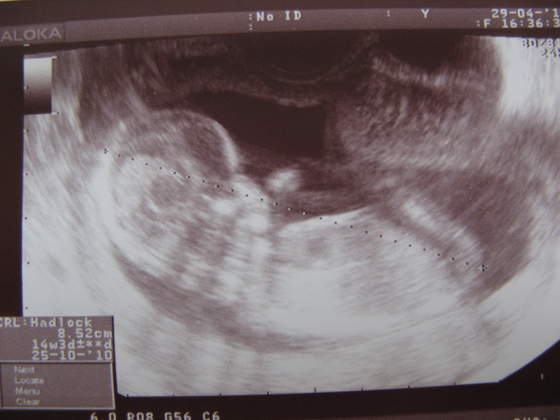

Mój Skarb z dzisiejszego usg;)

16-17tc.jpg

A to moja maleńka Lenka 11cm, 17 tydzień :)